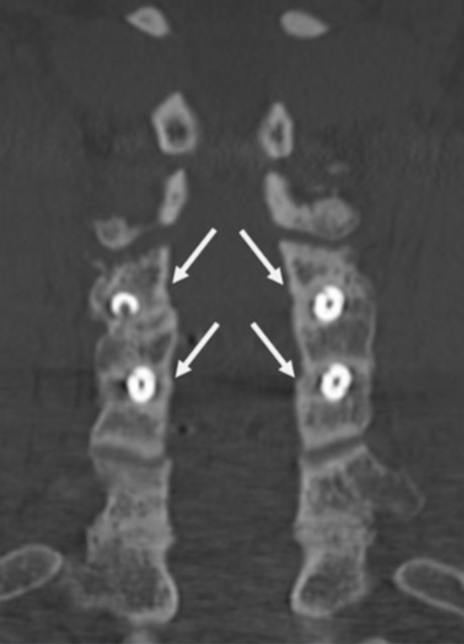

Coronal CT image showing circumferential bone bridging around the ION-C implants bilaterally.